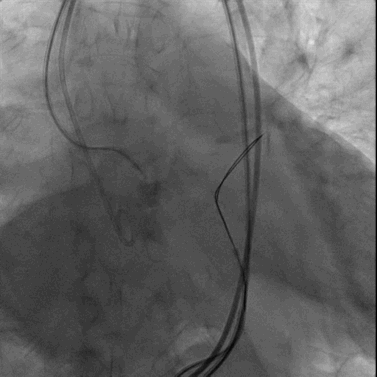

最终造影显示人工瓣膜位置理想,无明显中心或瓣周反流,升主动脉、主动脉弓及降主动脉均未见明显主动脉损伤征象。

术后主动脉根部造影